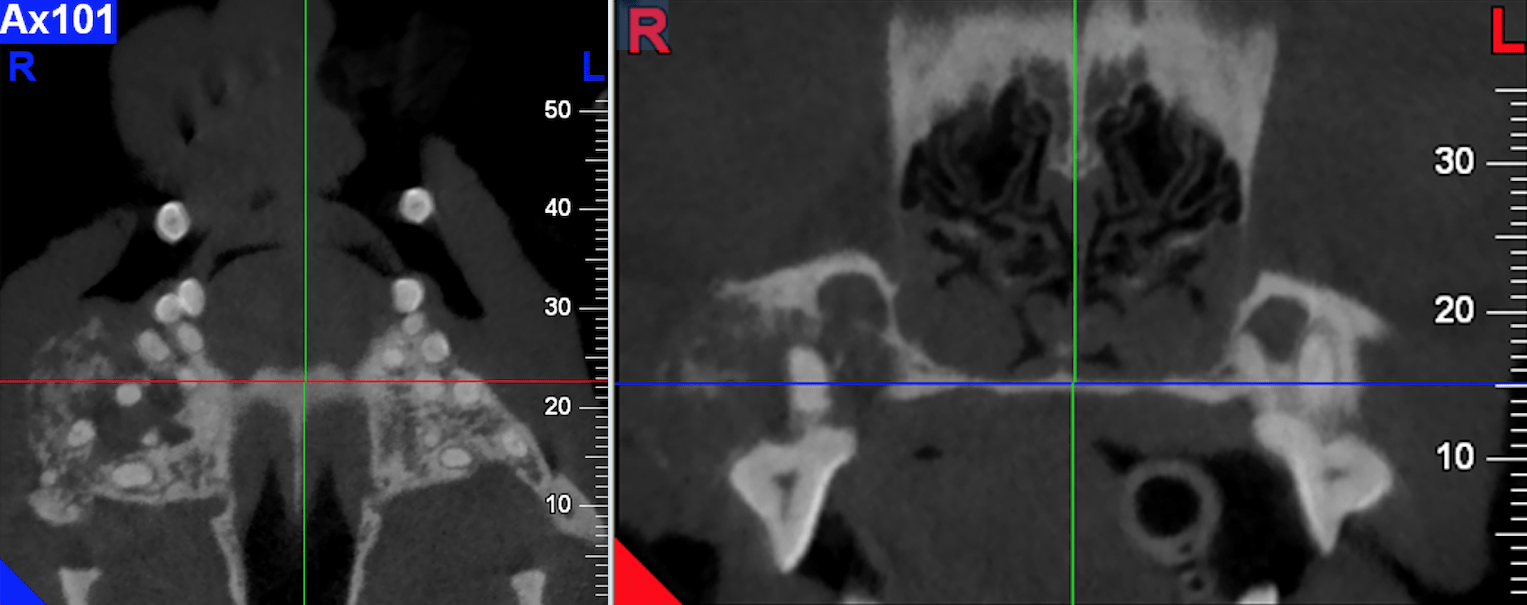

Identifier les glandes surrénales à l’échographie

Le Dr Florian Azoulay vous explique comment trouver les glandes surrénales à l’échographie. Lire la suite